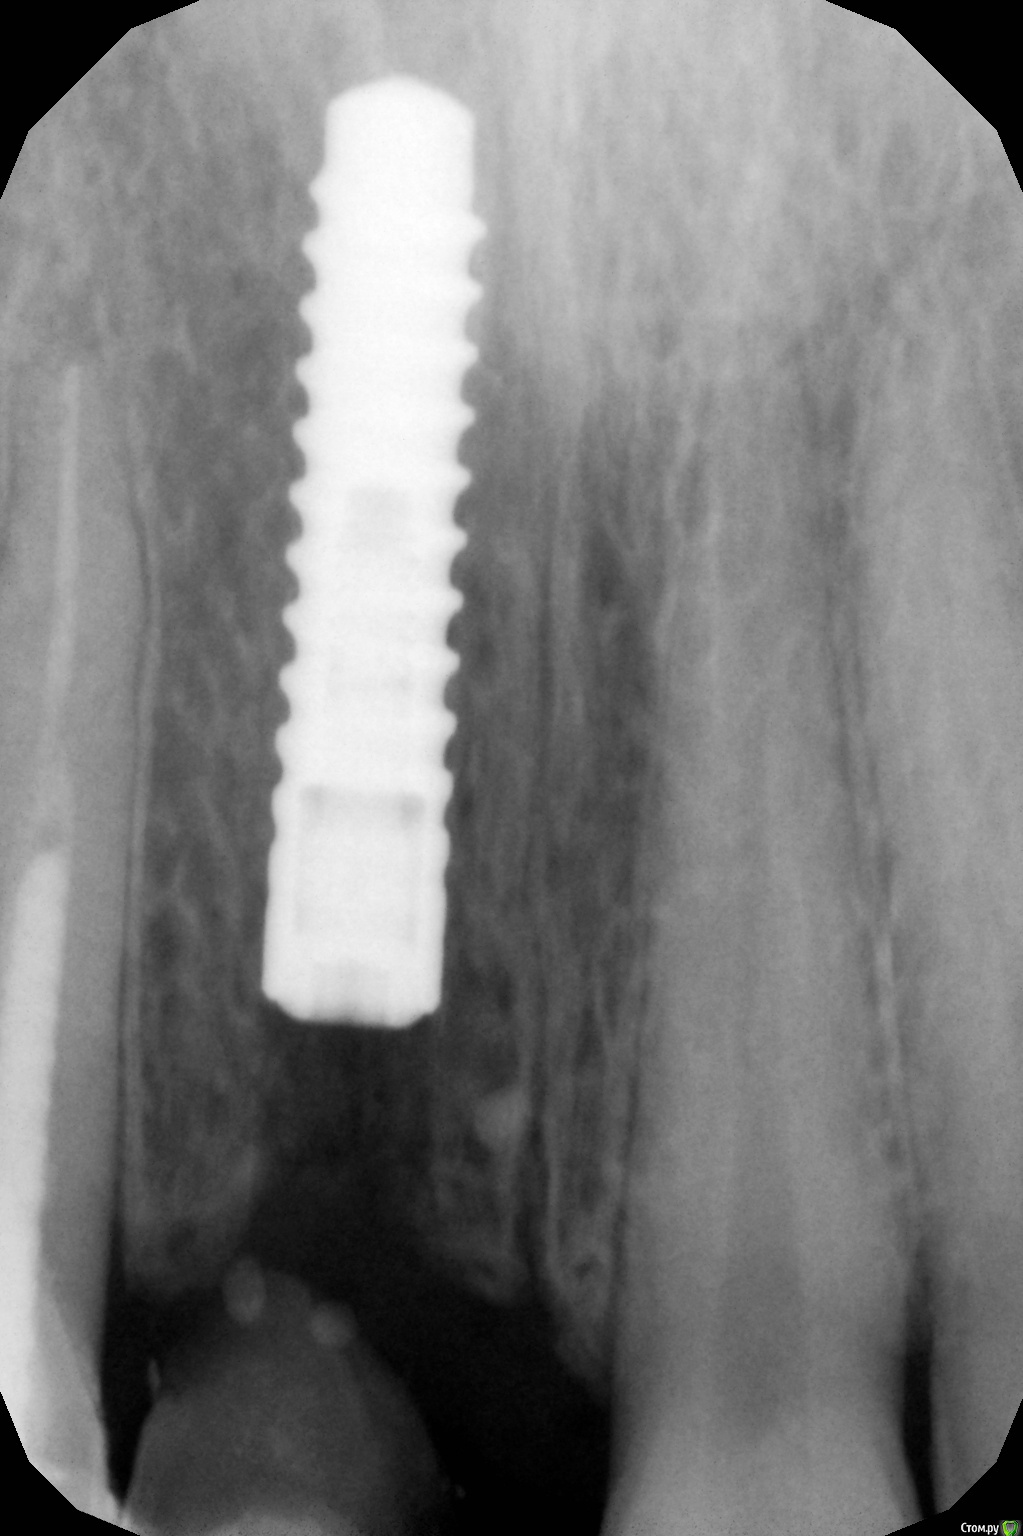

x4ex Опубликовано 16 октября, 2017 Поделиться Опубликовано 16 октября, 2017 (изменено) Три недели назад была имплантация Straumann Bone Level в области 11, вестибулярно подшит сст с бугра, заглушка и ушивание наглухо проленом 5/0. Сверху времянка на 12 с консолью в области 11. На контрольных осмотрах всё ок. Сегодня пришла с пузырём гноя вестибулярно. Со слов появился вчера, болит с позавчерашнего дня. Вскрыл, на коронарных полимпланта грануляции, вестибулярно, медиально и дистально кости нет, нёбно есть и апикально есть. Заглушку выкрутил, имплант не вышел. Выкрутил имплант ключом. В чём может быть причина?P.S. первая имплантация Straumann, абсолютно новым набором, строго по протоколу. Торк был около 30Нсм. Изменено 16 октября, 2017 пользователем x4ex Ссылка на комментарий

x4ex Опубликовано 16 октября, 2017 Автор Поделиться Опубликовано 16 октября, 2017 Графта не было. Насчёт удаления зуба не помню, возможно даже там первичная адентия была.Девушке 27лет и она пришла с коронкой на 12 с консолью на 11. КТ до есть, после только прицельный. Завтра всё добавлю. Имплант ставил субкрестально, примерно на 2мм, исходя из положения зенита соседнего зуба. Ссылка на комментарий

x4ex Опубликовано 17 октября, 2017 Автор Поделиться Опубликовано 17 октября, 2017 Диаметр был 3.3, вестибулярно кость была. Разрез был по гребню плюс внутрибороздковый на 12 и 21. Послабляющих не делал.Могло такую реакцию спровоцировать попадание инородного тела, скажем, волокна от стерильного материала? Ссылка на комментарий

x4ex Опубликовано 17 октября, 2017 Автор Поделиться Опубликовано 17 октября, 2017 Подозрительно не то слово. Клянётся, что проходит каждый год медосмотры и никаких патологий выявлено не было.Не знаю, как изменить шапку, поэтому добавлю снимки сюда. Ссылка на комментарий